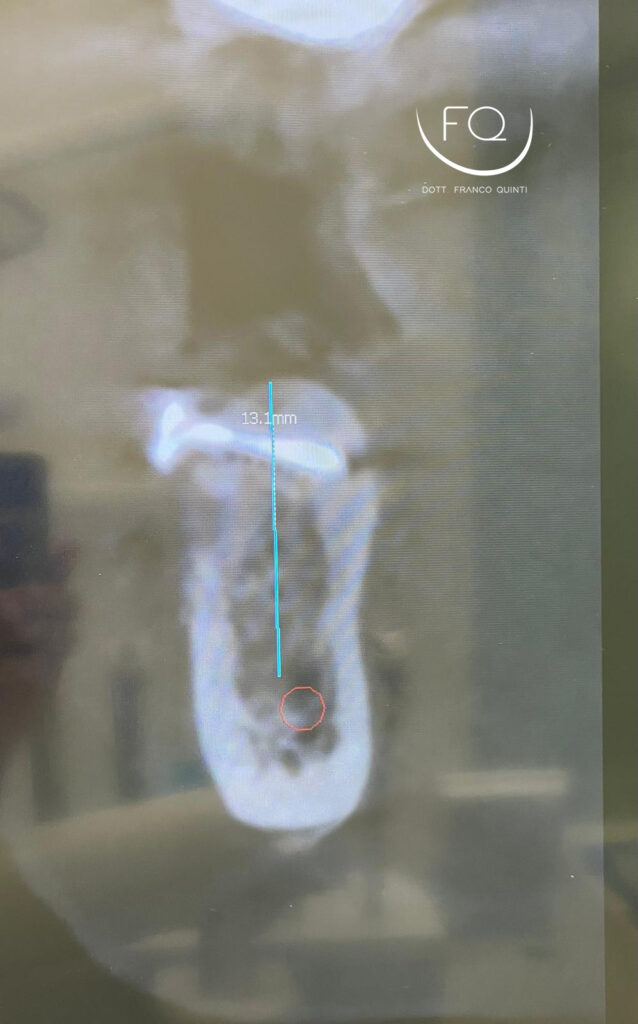

Oggi vi mostro un caso di GBR orizzontale in mandibola, trattato con un innesto a blocco fissato con vite da osteosintesi.

Dopo 4 mesi di guarigione è stato possibile procedere con l’inserimento di un impianto PRAMA di Sweden & Martina.